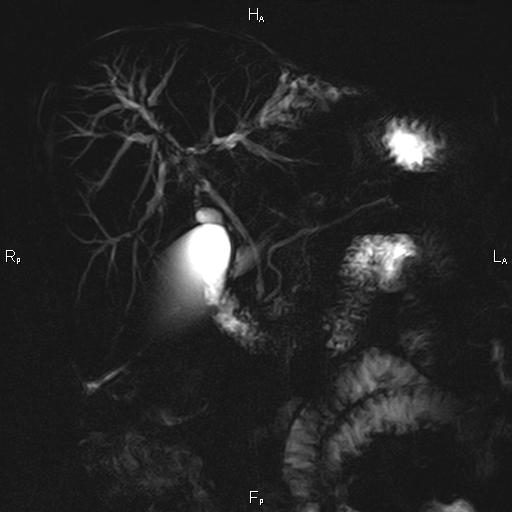

Ανώδυνος ίκτερος και παθολογικά ηπατικά ένζυμα. Ιστορικό πιθανής σκληρυντικής χολαγγειίτιδας

Μαγνητική τομογραφία.

Οι αρχικές εξετάσεις εκλογής, όσον αφορά τον απεικονιστικό κυρίως έλεγχο, σε ασθενή προσερχόμενο στο Νοσοκομείο με αποφρακτικό ίκτερο, είναι το υπερηχογράφημα και η αξονική τομογραφία. Οι εξετάσεις αυτές έχουν αποδειχθεί ικανές να προσδώσουν έμμεσα και άμεσα στοιχεία για τη διάγνωση του χολαγγειοκαρκινώματος, όμως κυρίαρχη εξέταση για την διάγνωση του χολαγγειοκαρκινώματος είναι η μαγνητική τομογραφία (MRI, MRCP, MRA).